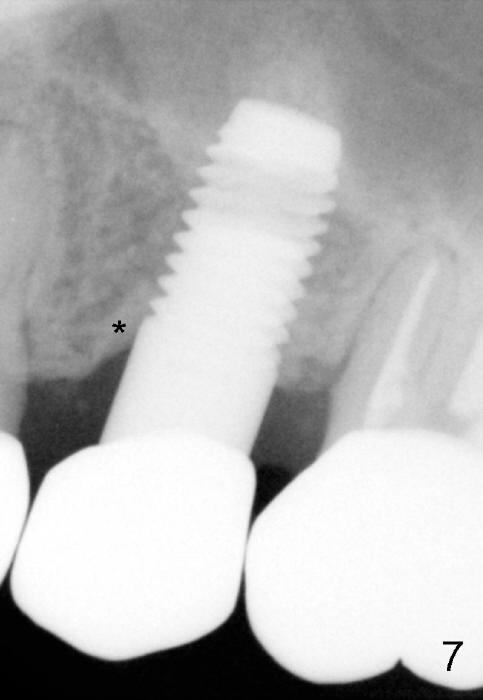

A 59-year-old lady used to have a 3-unit bridge in the upper left quadrant. A 4.5x6mm Bicon implant (Fig.1 B without extruding into the sinus) was placed in the atrophic pontic area 5 months earlier. When the abutment (A) was removed, the implant came out. The osteotomy was processed with a 4.5x14 mm tapered tap, which was unstable. When a 4.8 mm cylindrical tap was placed (past the sinus floor), it was tight (Fig.2). A 5x14 mm cylindrical implant (Fig.3 I) was inserted with elevation of the apparent sinus floor (>, no allograft used in case of sinus infection). Seven months postop, the density of sinus floor increases (Fig.4 <). The implant is stable and processed for crown (Fig.5 C, different view of the lifted sinus floor (<)). While sinus floor density is decreasing, the mesial and distal bone density is increasing 6 months (Fig.6), 1 year 6 months (Fig.7) and 3 year 6 months (Fig.8) post cementation.